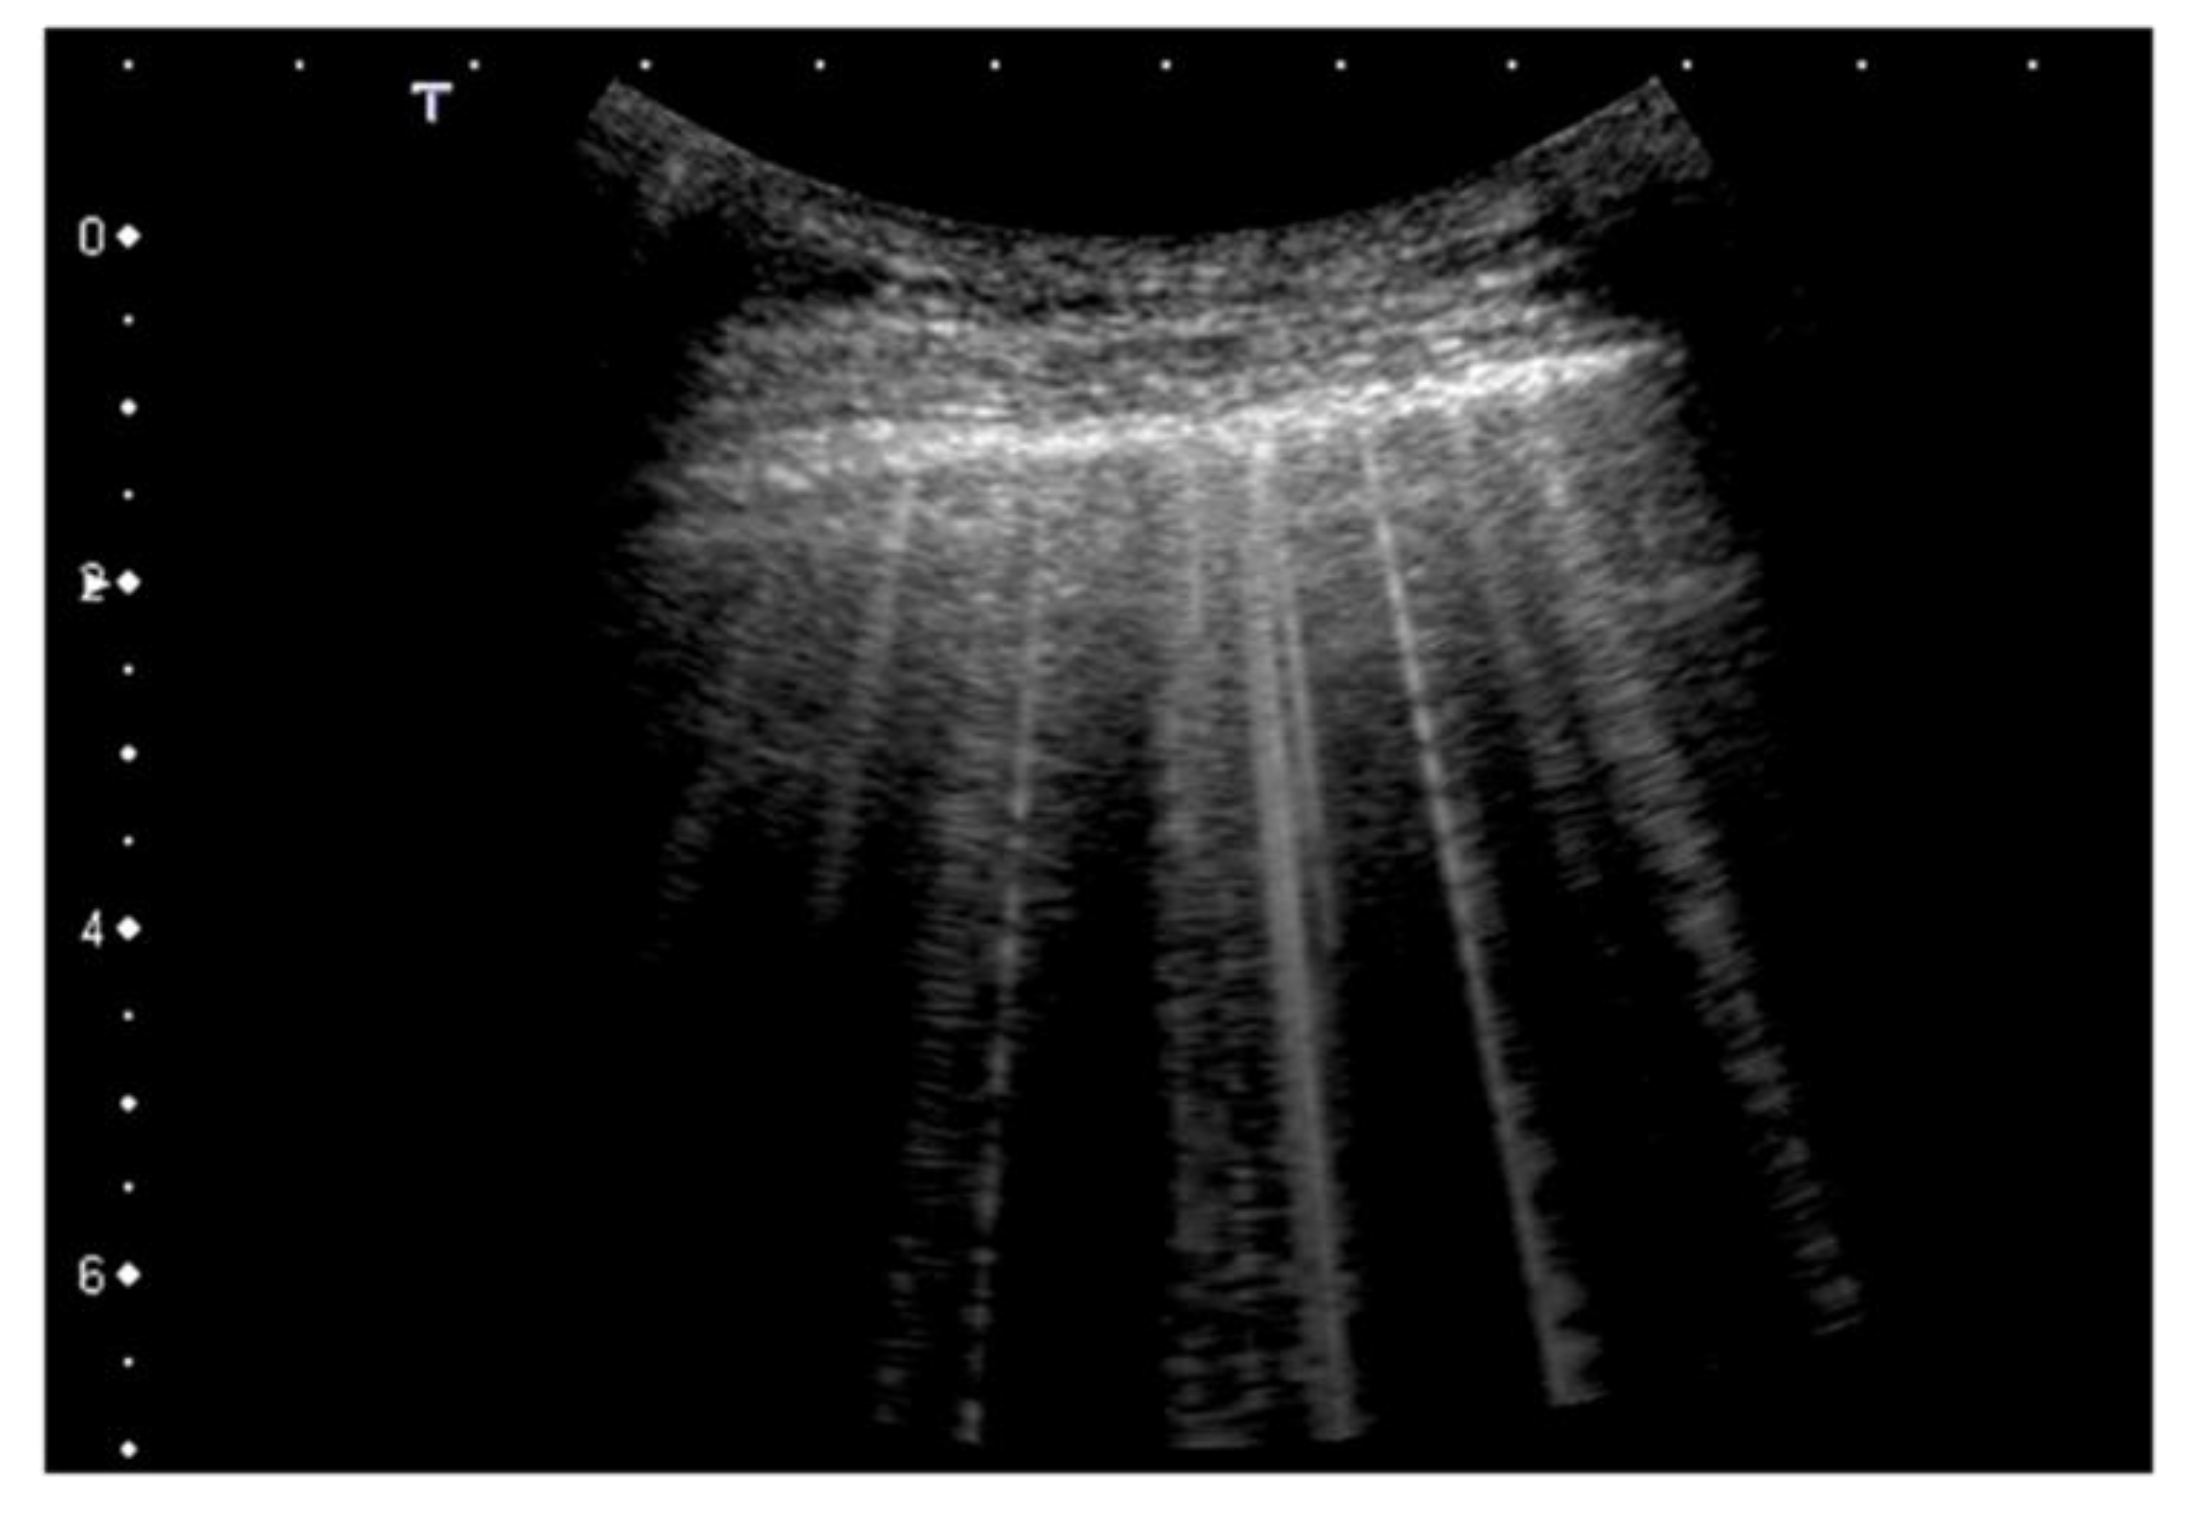

| 1 | Pleural line has slight alterations with sporadic vertical bright artifacts. The presence of relatively small acoustic channels due to focal interstitial thickening is speculated. |